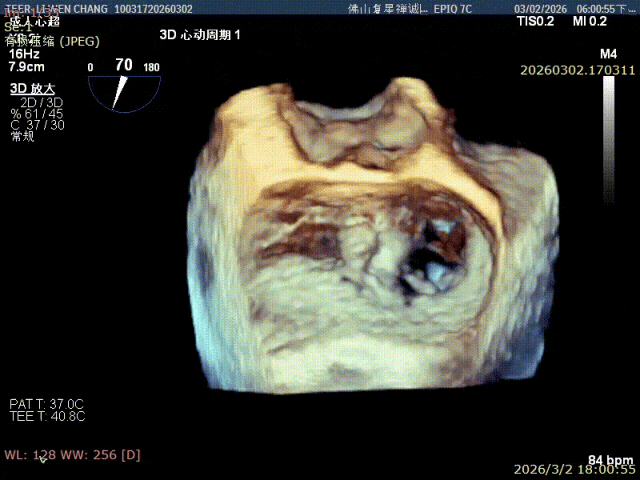

术前影像

3D 1区脱垂